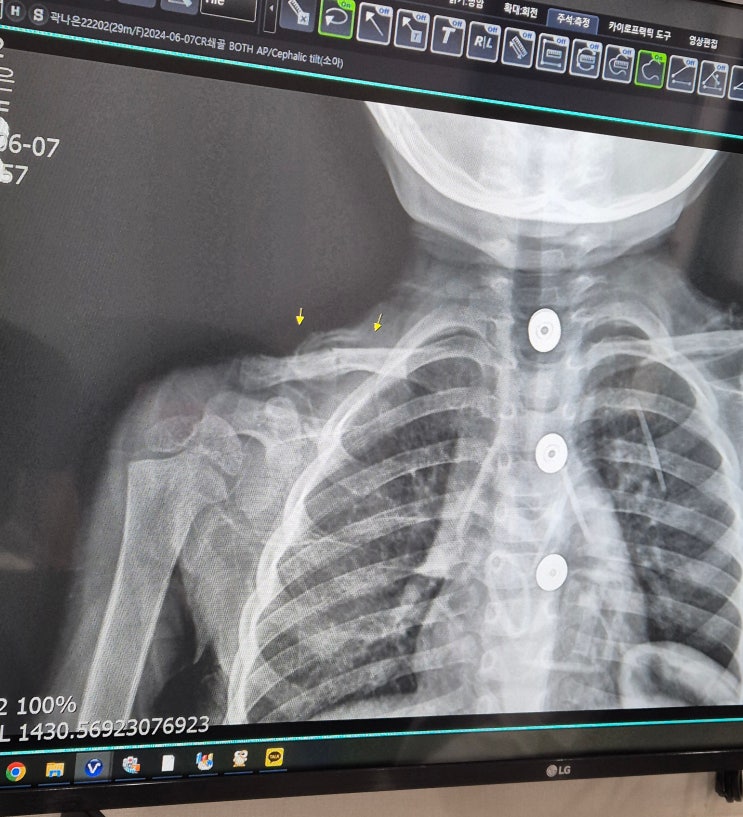

29개월 낙상 쇄골 골절 후 2주차 진료

28개월 아기 낙상쇄골 골절 후 1주차 진료

관련정보 28개월 아기 낙상 쇄골 골절 후 1주차 진료 ⓒ여낙낙 https://blog.naver.com/jhyeo1126/22345922...